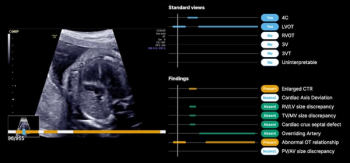

The latest FDA 510(k) clearance is for B-Right Views, an AI-enabled device, which provides automated detection of required views necessary for second- and third-trimester fetal heart ultrasound exams.